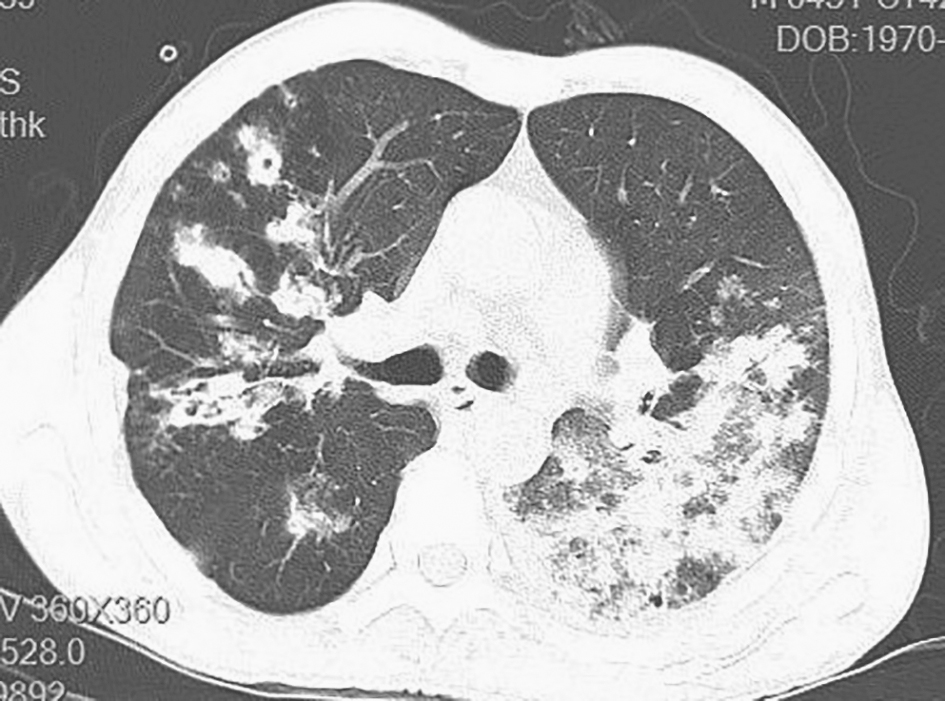

包括球孢子菌病、肺曲霉菌病、肺隐球菌病等,可导致肺部空洞形成,但胸部CT影像学表现缺乏特异性。典型的肺曲霉菌病可表现为晕征、空气新月征、曲霉菌球(图5);肺隐球菌病可出现肺实变、肿块及胸膜下结节影,其内可出现空洞(图6)。

图5 肺曲霉菌病胸部CT表现

胸部CT见双肺多发空洞,左肺空洞内可见曲霉菌球

图6 肺隐球菌病胸部CT表现

胸部CT见双肺多发结节影,其内可见小空洞,右下肺近胸膜处空洞明显